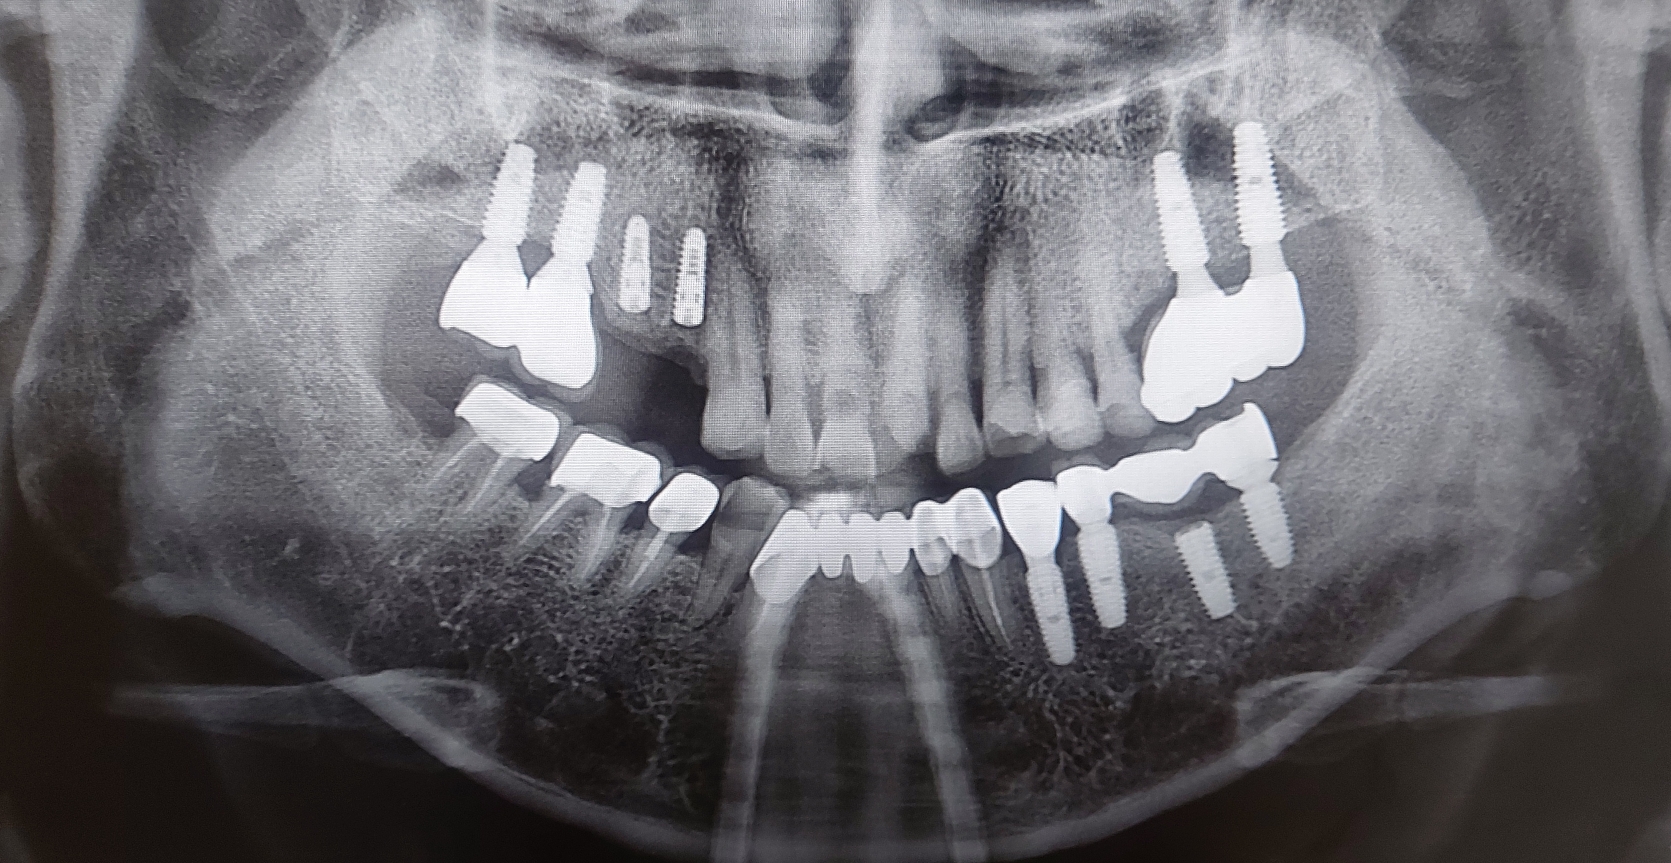

치아 뿌리에 우식이 있는 환자분이 과자봉지를 치아로 뜯다고 앞니 치아가 부러진것을 주소로 내원하셨습니다. 환자분 굉장히 당황해 하셨고 최대한 빨리 치아를 올려 드리기로 결정한 환자분입니다.

가장 중요한 부분은 atraumatic extraction 즉 외상이 거의 가지 않는 발치입니다. 저도 최대한 조심스럽게 발치할려고 노력하였지만 워낙 치아가 뼈와 유착이 되어 있어서 발치시 애를 많이 먹었습니다.

발치를 시행하고 UV임플란트를 식립하였습니다. 그리고 빈공간에 인공뼈를 이식후 봉합 시행하고 바로 구강스캐너를 이용하여 인상채득을 시행하였습니다. 수술 날짜가 3월 20일 오후경이고 오늘 3월 22일 치아를 넣어 드렸습니다.